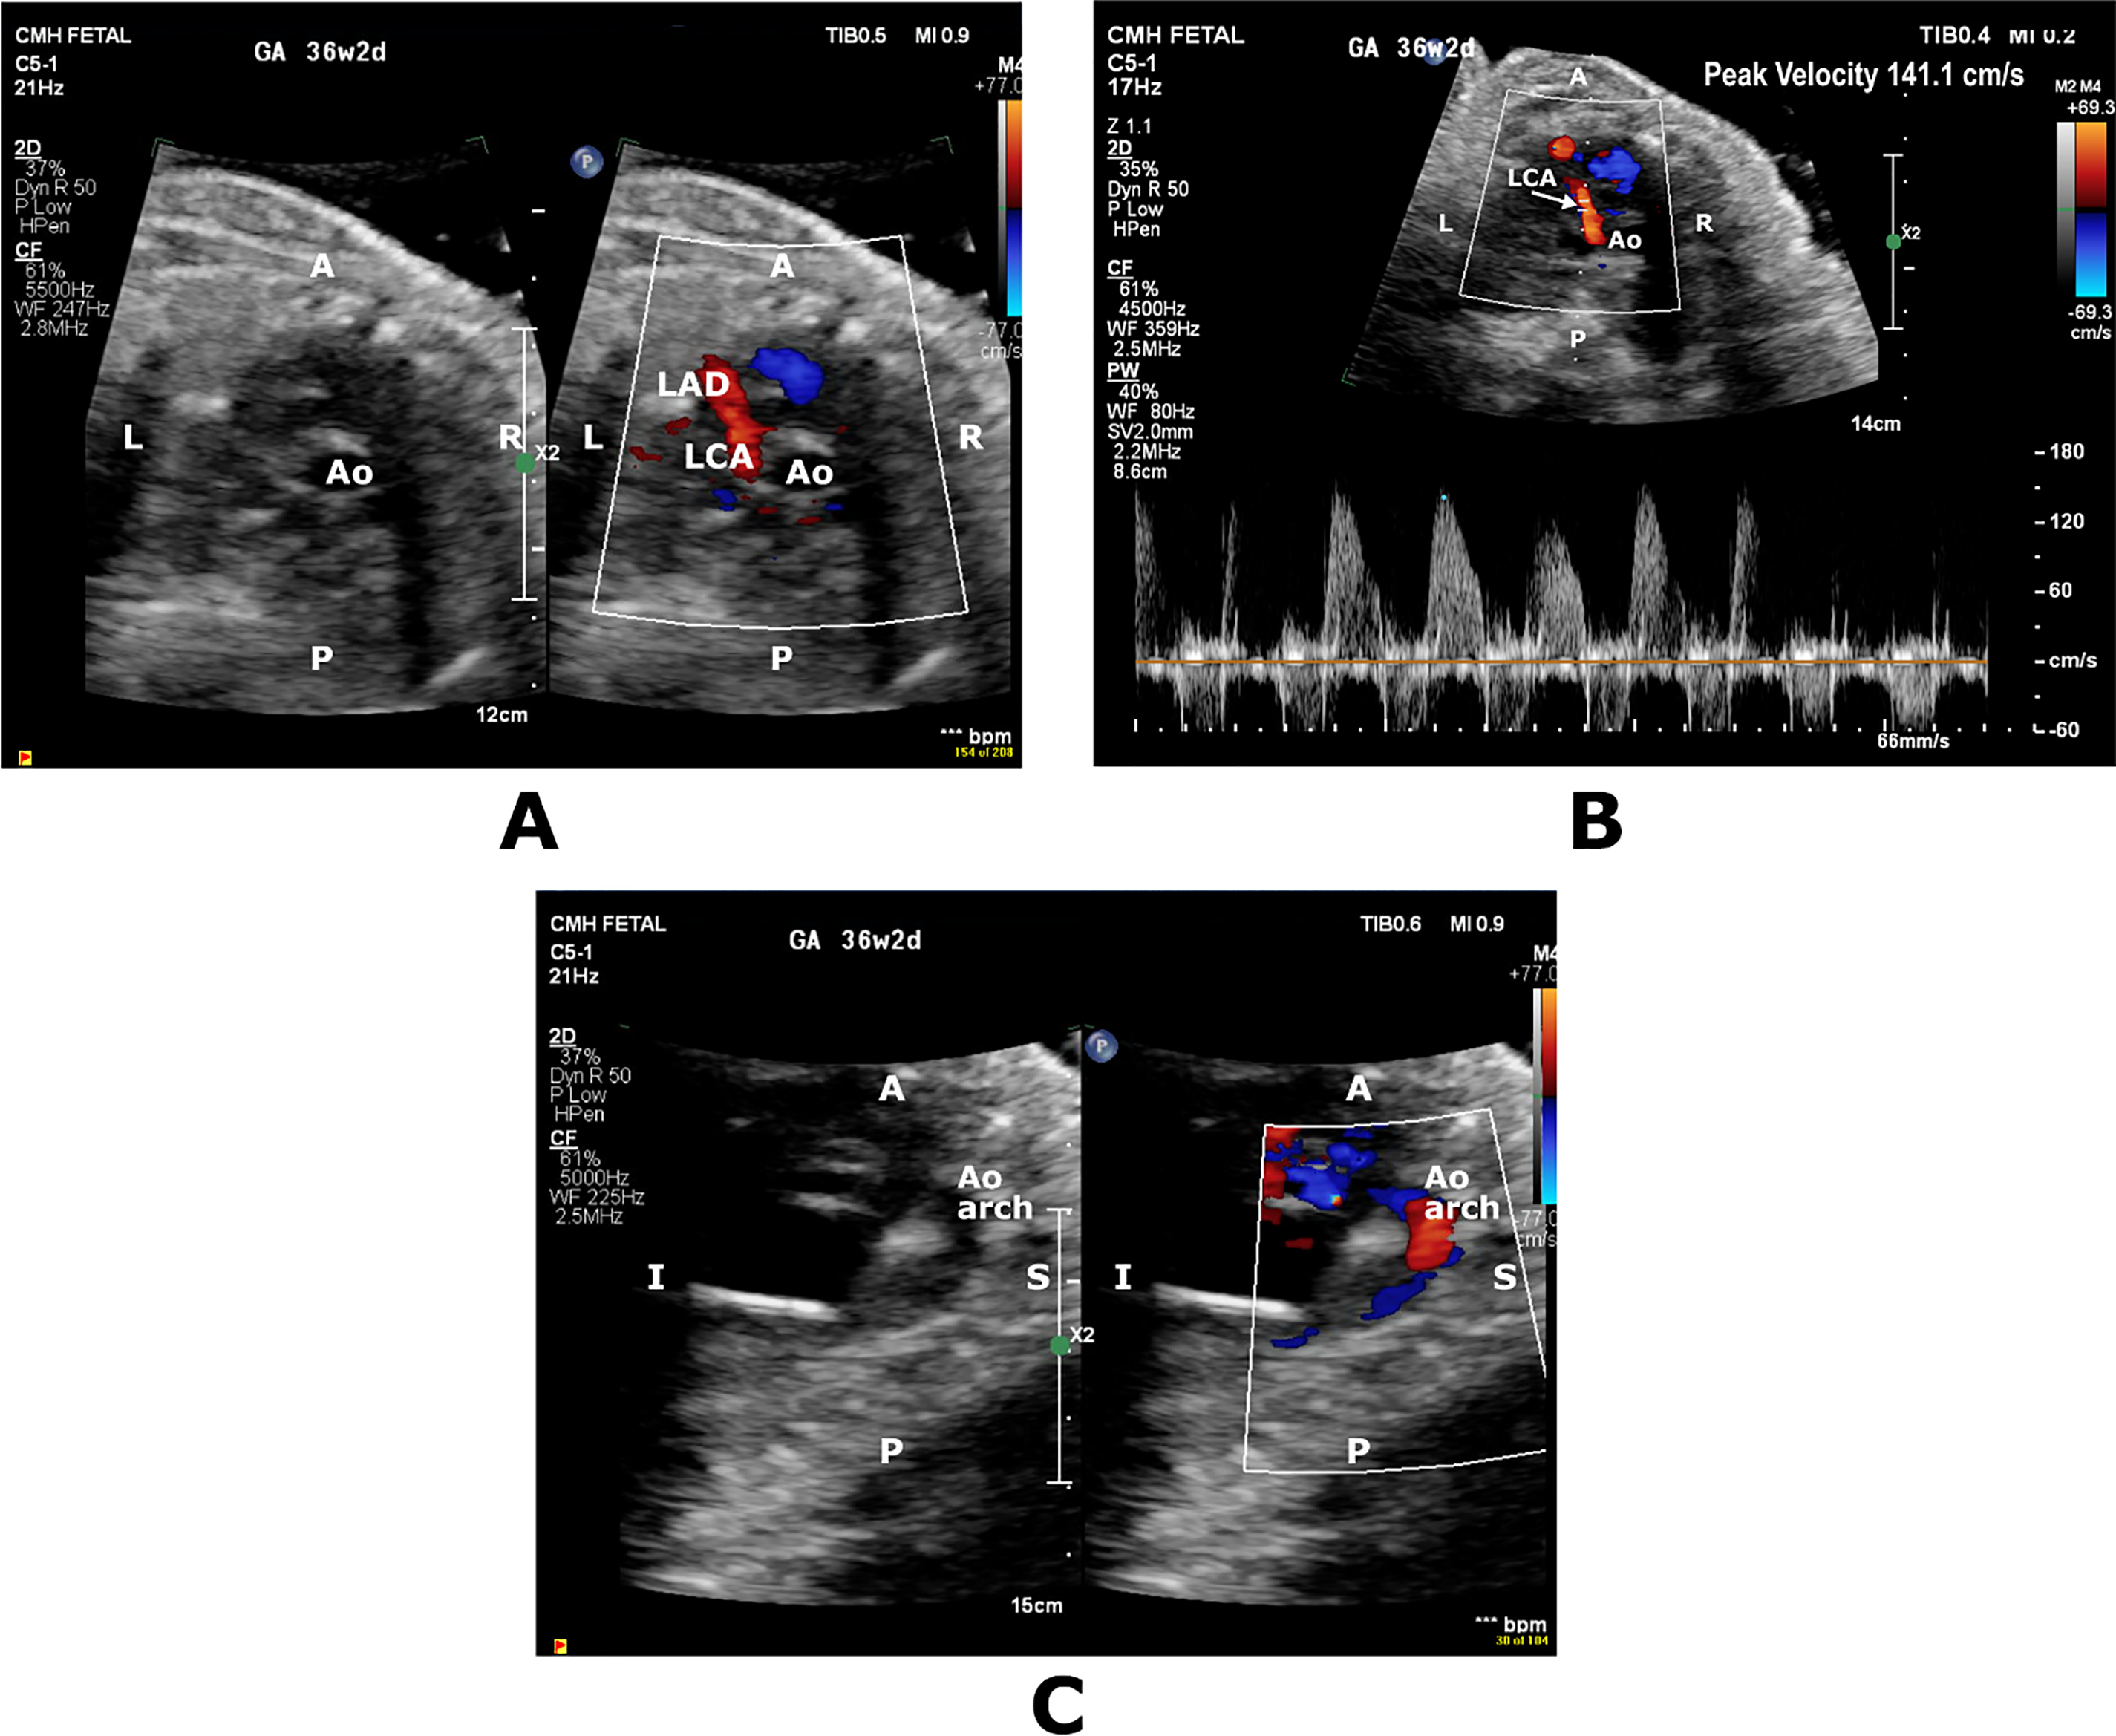

Fetal referral and FE for suspected CHD at 36 weeks’ GA demonstrated membranous ventricular septal defect (VSD) and mildly dilated right heart chambers. There was qualitatively normal biventricular systolic function with biphasic inflow Dopplers. Presence of dilated left main and left anterior descending (LAD) coronary arteries in combination with a dilated CS and retrograde flow in the transverse aortic arch led to suspicion for a CAF diagnosis (Fig. 2). PWD of the UA and MCA showed PI of 1.79 (>95th percentile) and PI 1.19 (<5th percentile), respectively and a CPR of 0.66 (<5th percentile). UV PWD showed pulsations. A DV PWD could not be obtained. Emergent C-section was performed the next day due to worsening extracardiac fetal Dopplers and non-reassuring fetal heart rate pattern, delivering a male infant weighing 2530 g (33rd percentile) with Apgar scores of 5,8. Postnatal echocardiogram confirmed the prenatal diagnoses but revealed normal-sized coronaries and no CAF. Biventricular systolic function was normal with LVEF of 55%. Placental pathology revealed histologic features of fetal and maternal vascular malperfusion. UA pH and pO2 were abnormally low at 7.1 and 12 mmHg, respectively. Successful membranous VSD closure was performed at 4 months of age.

Figure 2: Short axis color-compare image and pulsed wave Doppler (A,B) showing prominent diastolic flow in the territory of left coronary artery (LCA) and left anterior descending coronary artery (LAD). Sagittal color-compare image (C) showing flow reversal in the transverse aortic arch (Ao Arch). A, anterior; Ao, Aorta; I, inferior; L, Left; P; Posterior, S; Superior, R; Right

In Case 2, the suspicion of a CAF from LAD to the CS was raised in presence of retrograde flow in the transverse aortic arch and multiple VSDs. The UA, MCA, and UV indices were suggestive of in utero distress, albeit with normal cardiac function and no growth restriction. Baschat et al. [2] have suggested that prominent CA flow signifies hemodynamic deterioration in fetuses with IUGR and that this finding coincides with worsening extracardiac Dopplers. They postulate that sudden ability to visualize prominent CA flow is secondary to acute-on-chronic hypoxemia response. Our case demonstrated similar findings, and, in retrospect, awareness of this possibility may have led us to consider that, even without IUGR, these findings might be indicative of heart-sparing effect rather than a CHD-associated CAF.